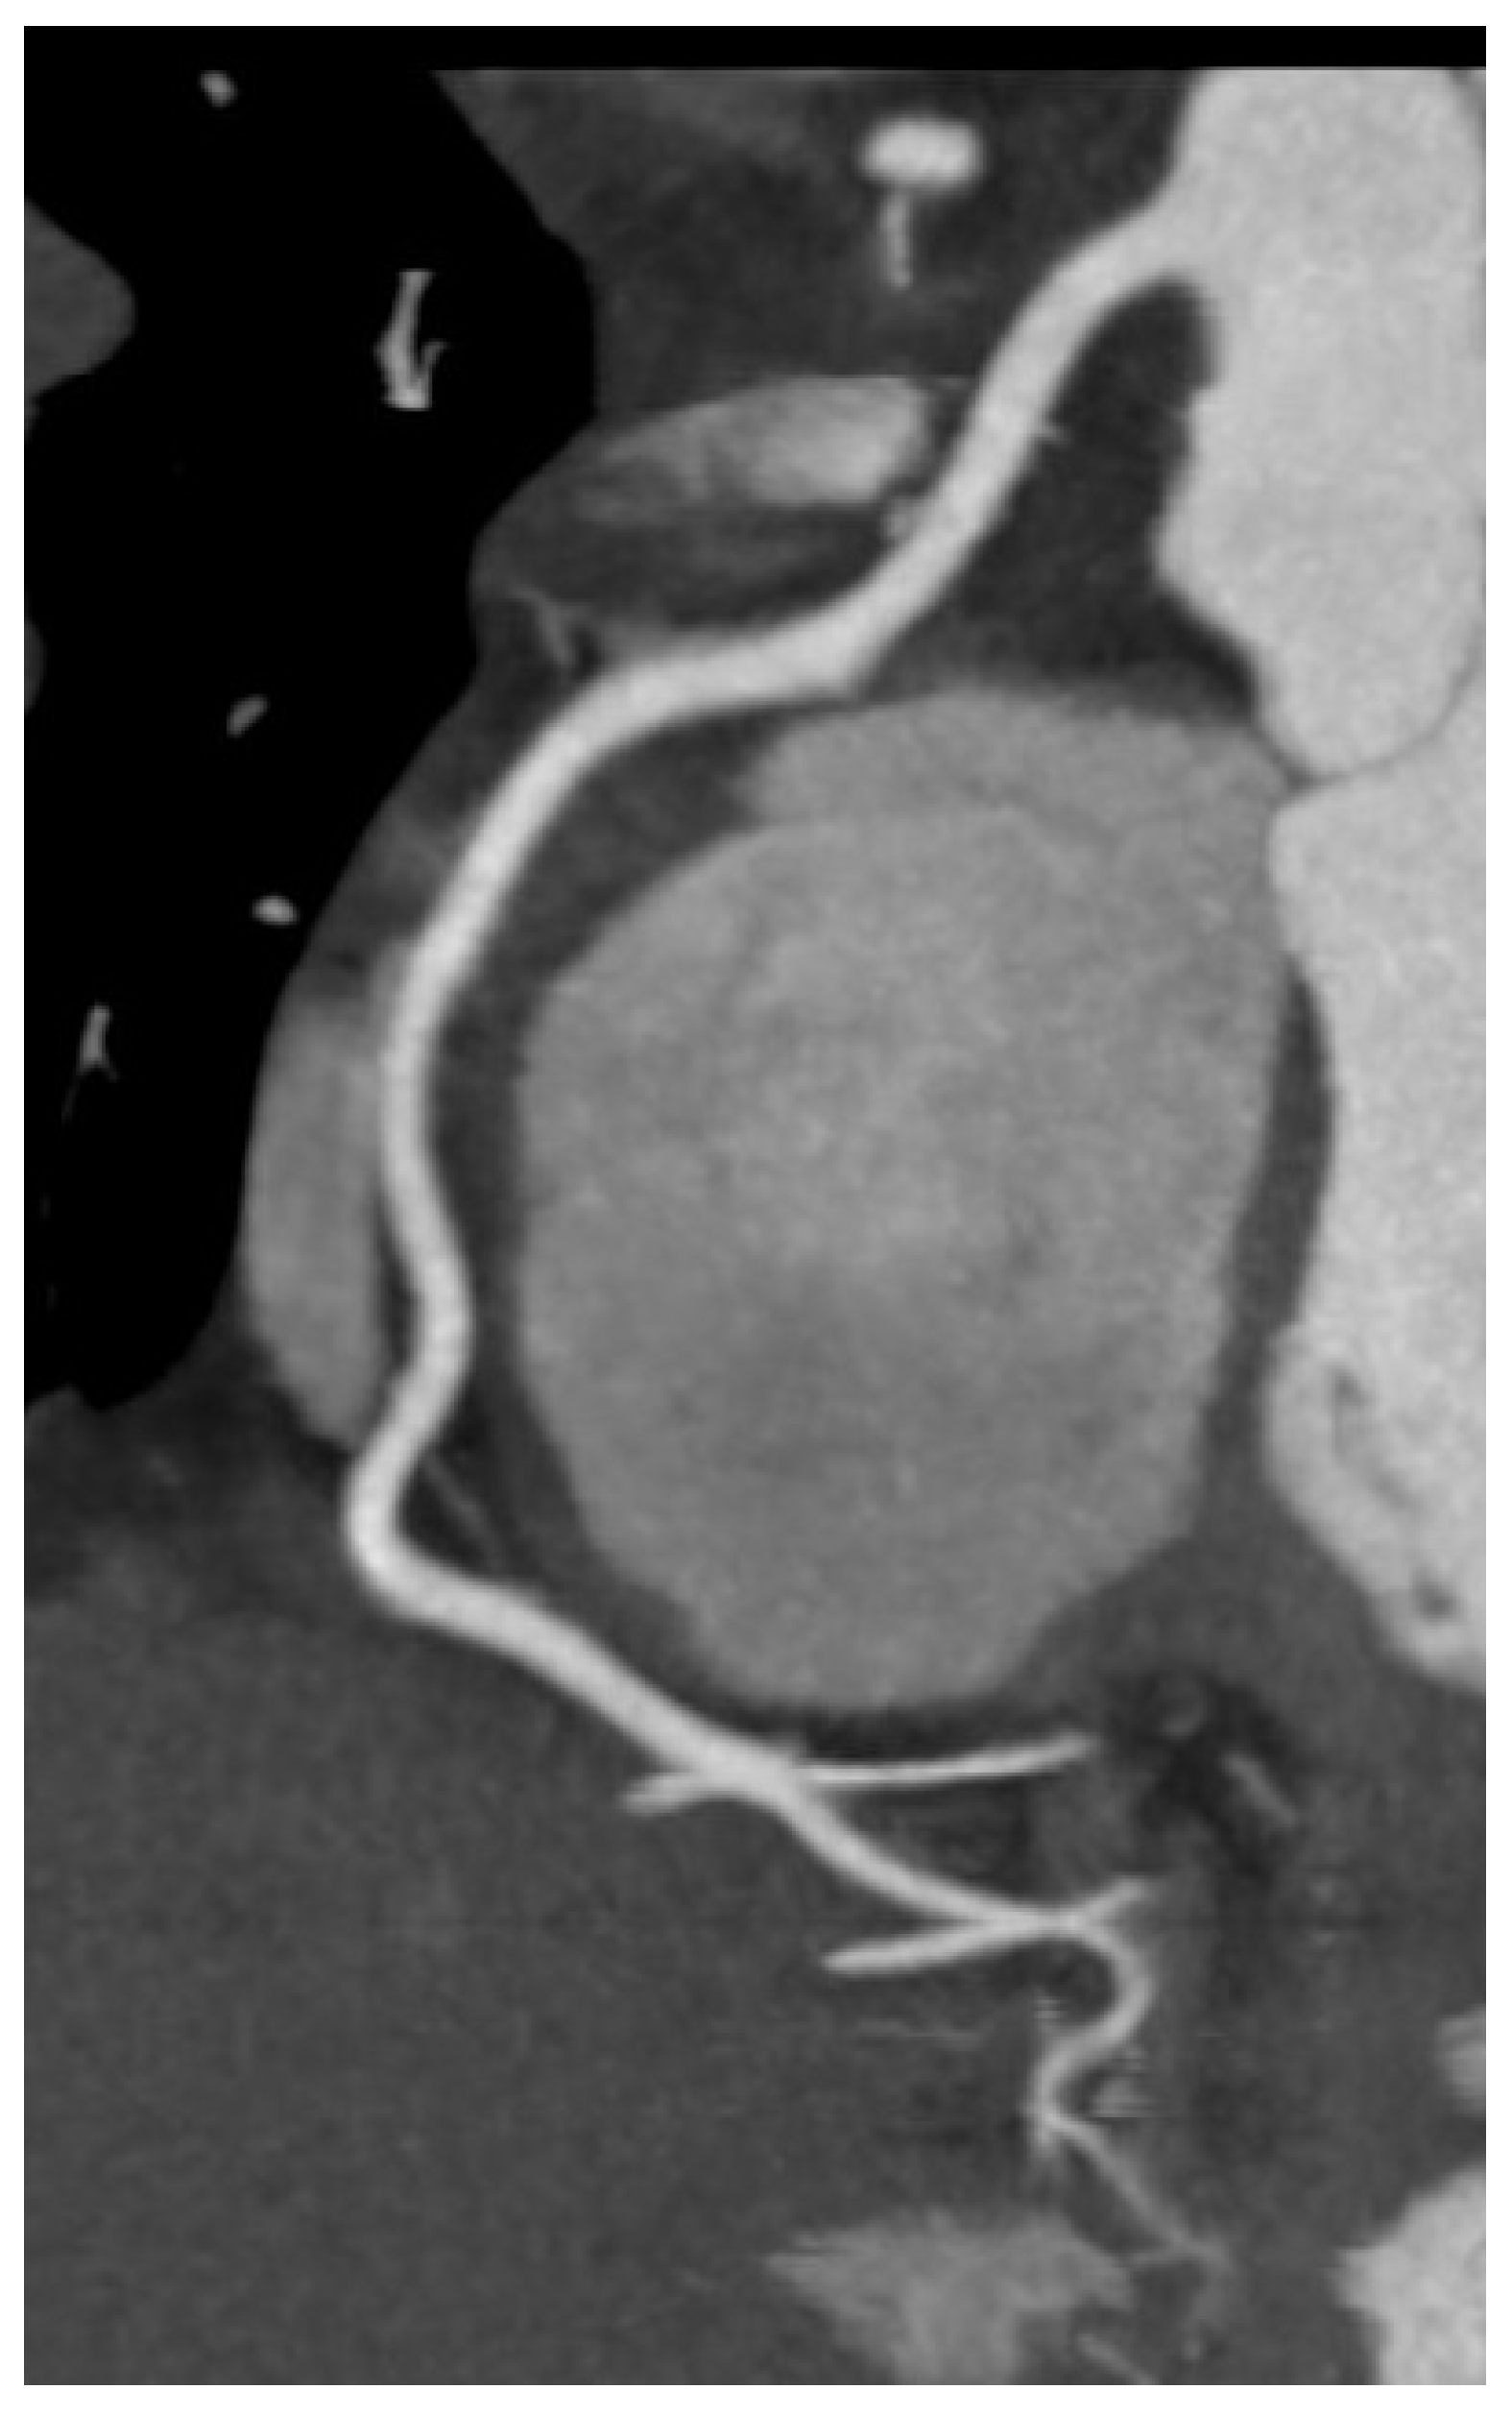

7. Role of Cardiac CT in Heart Failure

Cardiac computed tomography (CT) assumes an increasingly significant role in the diagnostic evaluation and management of HF, particularly when there is a necessity to assess coronary anatomy, structural heart disease, or pericardial pathology. Coronary CT angiography (CCTA), a non-invasive, very sensitive technique is the major use of cardiac CT in HF for identifying or ruling out coronary artery disease (CAD), a major cause of HF. Among patients with low to intermediate pre-test probability of CAD, CCTA has a great negative predictive value and can reliably rule out obstructive lesions with great accuracy (Figure 8) [65,66].

Particularly when MRI is contraindicated or unavailable, CT helps for exact assessment of cardiac and extracardiac structures including ventricular volumes, wall thickness, and calcifications. In cases of suspected constrictive pericarditis, CT aids in the differentiation from restrictive cardiomyopathy by visualizing pericardial thickening and calcification [68,69].

Even with these benefits, cardiac CT suffers limitations including radiation exposure, dependence on iodinated contrast (which is worrisome regarding renal insufficiency), and reduced soft tissue definition relative to MRI. Nevertheless, in the right clinical setting, cardiac CT presents a useful supplementary tool in the comprehensive assessment of HF that offers fast, detailed anatomical information impacting diagnostic and therapeutic avenues.